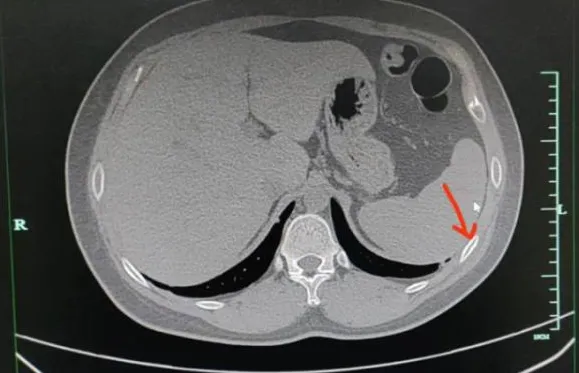

▲聶先生咳斷2根肋骨。(圖/翻攝自閩南網)

醫師一看他的CT發現,「患者的右側第五、第六肋骨都骨折了,肋骨骨折與其他骨折不同,它不承受重量,所以在靜止狀態下通常沒有疼痛感。但當肋骨受到外力按壓或胸廓活動較大時,如咳嗽或深呼吸,就會引發疼痛。」